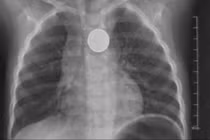

Tưởng như chỉ có trong phim, song mới đây, các y bác sĩ Bệnh viện Hữu nghị Việt Tiệp đã xử lý một ca dị vật đặc biệt cả chiếc bàn chải đánh răng nằm trong thực quản.